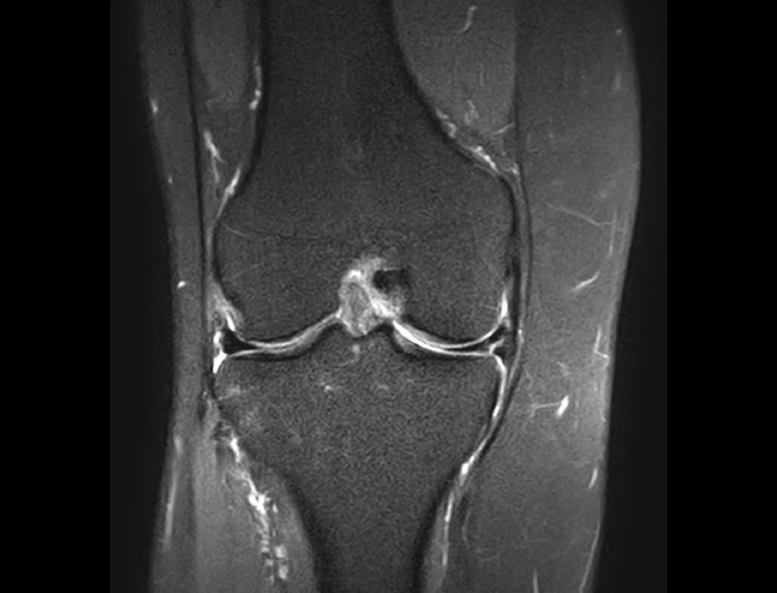

4.3. Osteocondritis

En la osteocondritis se aprecia una lesión subcondral caracterizada por resorción ósea, colapso y la formación de un secuestro.

El estudio por RM es una herramienta valiosa para diagnosticar e identificar las lesiones del cartílago. Conocer el aspecto del cartílago y saber cuánto y cuándo se lesiona, basándose en las clasificaciones actuales, permiten al radiólogo proporcionar la máxima información al clínico(20).

Figura 53. Corte de secuencia sagital (A) y axial (B) T2 Fat-Sat de RM de rodilla: lesiones osteocondrales en el fémur y la rótula.

Numerosos estudios demuestran la utilidad de la RM para definir la estabilidad o inestabilidad de la lesión en la osteocondritis, destacando su carácter no invasivo y la capacidad de valorar la progresión y la respuesta al tratamiento(21)(Figuras 53 y 54).

Figura 54. Corte de secuencia T1 y T2 Fat-Sat coronal de resonancia magnética: gran osteocondritis en el cóndilo femoral interno con edema en la medular adyacente.